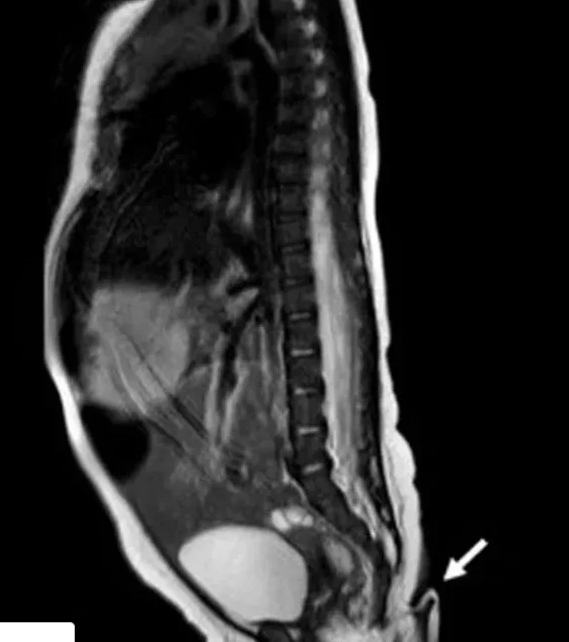

Kuyruğa benzeyen yapının saç ve deriyle kaplı olduğu fark edildikten sonra röntgen çektiler. Kuyrukta herhangi bir anormallik veya kemik yapısı bulgusu bulamadılar. Bu, kuyruğun zamanla vücuttaki tüm kullanımlarını yitirmiş bir apendiks anlamında işlevsiz bir kuyruk değil, “gerçek bir kuyruk” olduğu belirlendi. Doktorlar vakayı "Son derece nadirdir" şeklinde tanımladı.

Doktorlar omurga sorunlarını eledikten sonra, kız bebek iki aylık olduğunda bir pediatri ve genel cerrahi ekibi tarafından yeniden değerlendirildi. Doktorlar yaşa göre yeterli kilo alımı ve büyüme olduğuna ikna olduklarında kuyruk yapısının uzunluğu 0,8 cm arttı. Deri lezyonlarına dair hiçbir kanıt olmadan, kuyruğun çıkarılmasına ve bölgenin Limberg plastisiyle yeniden yapılandırılmasına karar verildi.